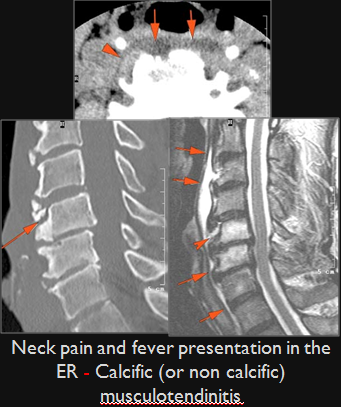

There is edema/abscess within in the prevertebral or paravertebral spaces.

There is erosive process involving the disc spaces or other components of the spine.